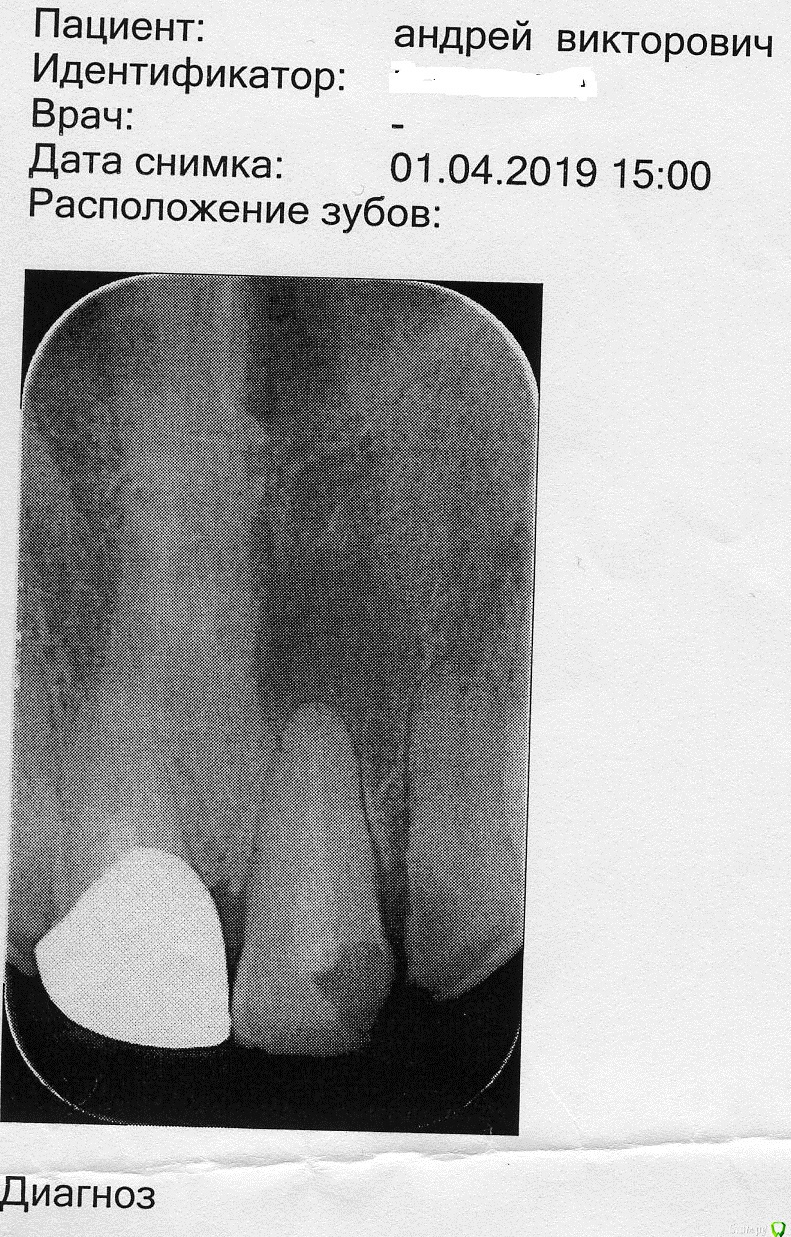

Андрей67 Опубликовано 12 марта, 2020 Поделиться Опубликовано 12 марта, 2020 С год назад обнаружил на десне шишку. Не болела и не беспокоила. В апреле 2019 пошел к врачу у которого лечусь давно и ему, в принципе, доверяю. Зуб рассверлили, почистили, положили лекарство. Так продолжалось раз 5. Потом поставили постоянную пломбу.(снимки №1 и №2)Для перестраховки сходил к лицевому хирургу, показал снимки, посмотрел, пощупал и сказал, что всё нормально. Говорит, что такая опухоль проходит долго, до полугода. Вроде как со временем и меньше стала, потом опять больше. Вернее, день ото дня размер может меняться, то больше то меньше.В феврале этого года оять пошел к своему врачу. Сделали снимок (снимок №3) Говорит, странно, что не рассосалось. Но раз не болит и не мешает, так и живи. Да, пригласила хирурга для консультации. Он сказал, что может разрезать и почистить, но гарантии никакой не даёт.Диагноз ставят - киста. Так ли это на самом деле? Нужно ли лечение и какое или так жить? Ссылка на комментарий